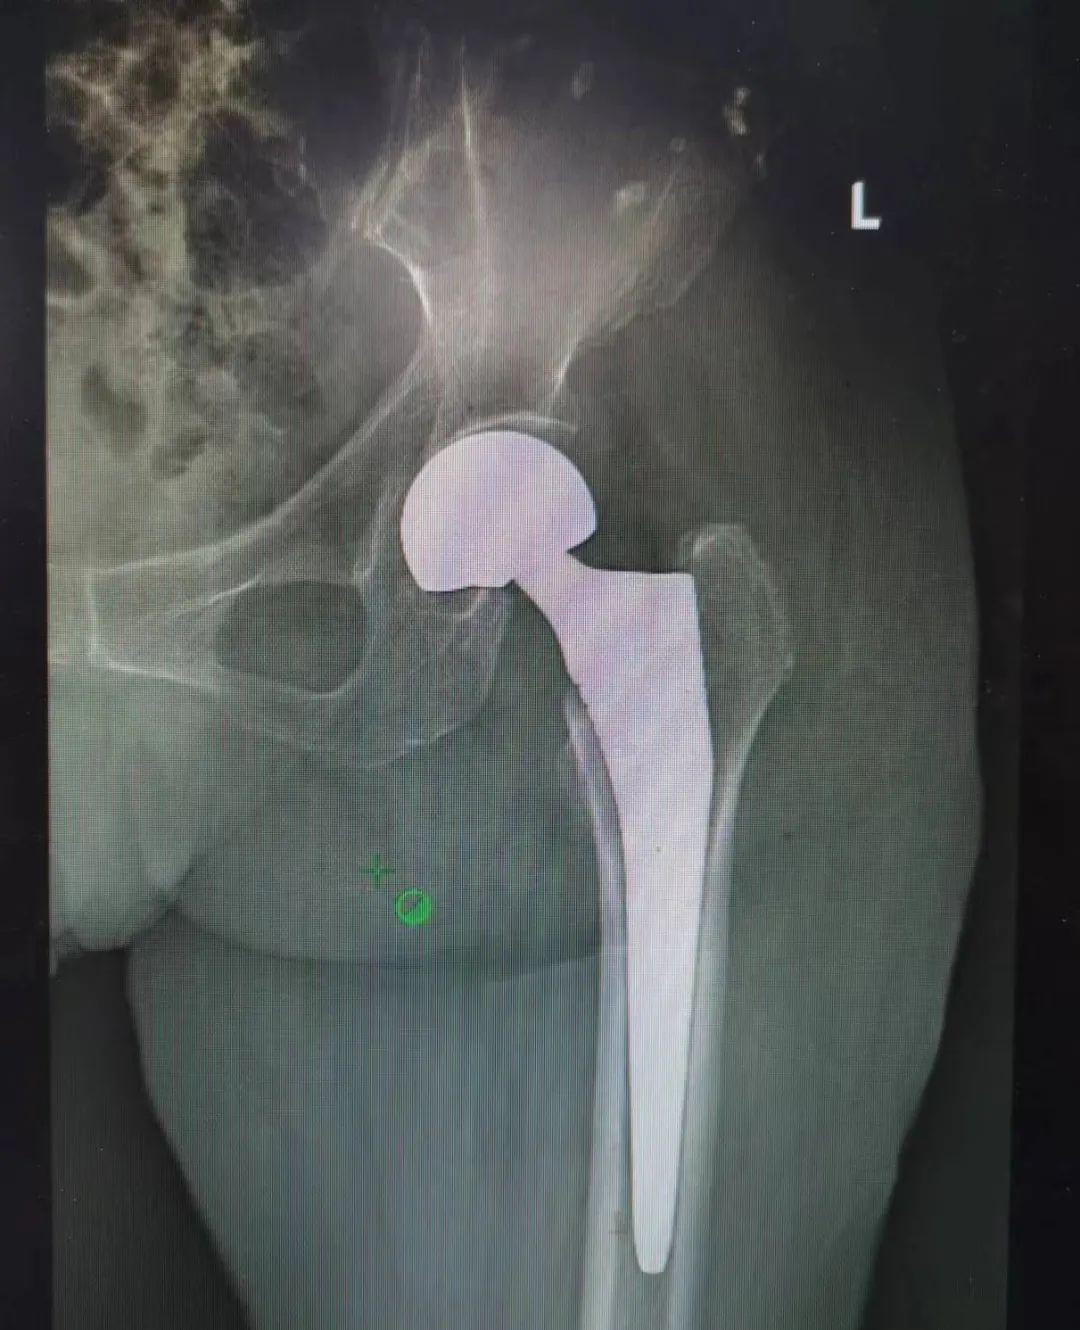

手术当天非常顺利,陕西冶金医院骨科赵学刚主任主刀,为患者实施人工半髋关节置换术。

▲ 图:术后X光片

骨科团队不仅在髋关节置换手术技术上积累了丰富的经验,术后护理也颇有心得。手术后回到病房。老人家的心脏功能十分脆弱,因此术后的照料十分重要。在陕西冶金医院骨科郗斌护士长护理团队的无微不至的照料下,王奶奶平稳度过术后。